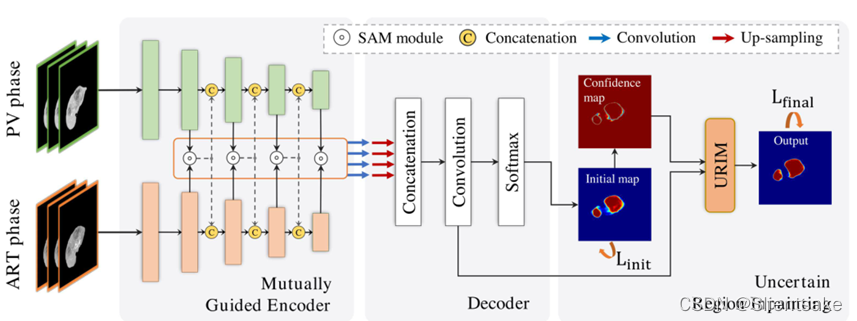

总的来说,网络将PV切片和ART切片都作为输入,并产生原发PV阶段的肿瘤分割。图1示出了所提出的网络的概况,其主要包括三个部分。

图1:图示提出的多期肝脏肿瘤分割网络

相互引导编码器部分以ResNeXt-50为主干。它使用两个路径,即PV流和ART流,来提取特定相位的特征。两个流的卷积块被表示为

B(I)pv B(I)art(I∑{ 1,2,3,4,5})。为了整合跨阶段信息,来自B(I)PVc和B(I)ART(I∞{ 2,3,4,5})的特征通过SAMs以双向方式聚合。通过这样做,这两个流提供了相互帮助的信息,从而相互指导它们的特征提取。

解码器部分将来自编码器的四级聚集特征作为输入,并产生初始概率图。为了合并多级特征,使用双线性插值对所有输入进行上采样,并通过级联和卷积进行融合。

解码器顶部的不确定区域修复部分旨在细化初始特征图中的不确定区域。直观地说,它使用有信心的像素来修复相邻的不确定像素。为了实现这一点,允许不确定的像素使用一种建议的局部置信卷积(LC-Conv)运算来吸收周围的区别特征。最终预测采用细化特征。

损失函数包括两个交叉熵损失(见图1),Linit在初始分割和地面事实之间,Lfinal位于最终预测和地面事实之间的。Linit和Lfinal最终对总损失的贡献相等。方法是基于PyTorch 1.5.0实现的,并在NVIDIA GTX 2080 ti GPU (12 GB)上进行了训练。使用SGD优化器来训练我们的网络,初始学习速率为5×104,每50个周期除以10。